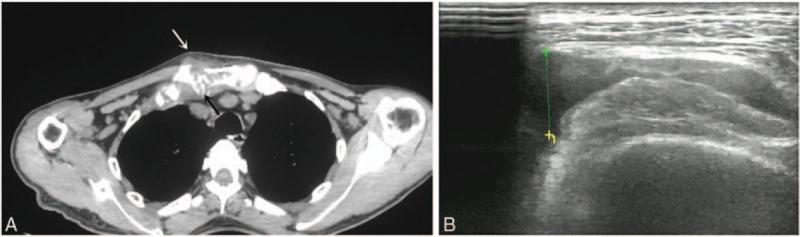

Early diagnosis and prompt withdrawal of all suspected drugs is a key tenet of the treatment of DRESS. Our case report highlights the risks inherent in delayed diagnosis of DRESS and the challenges in the clinical management of this condition. Pulmonary manifestations with radiological changes on chest X-ray and CT can be seen in DRESS. These changes need to be differentiated from those caused by pulmonary infections. Clavicular osteomyelitis infected with MRSA may be caused by iatrogenic injury during subclavian vein catheterization. This type of MRSA infections should be treated for 4 to 6 weeks. Blood eosinophilia could be a useful marker of disease progression and treatment response in patients with DRESS. However, more experience and clinical evidence is needed to confirm this.

早期诊断并立即停用所有可疑药物是治疗DRESS的关键原则。我们的病例报告强调了DRESS延迟诊断所固有的风险以及这种疾病临床管理中的挑战。DRESS可出现胸部X线和CT上有放射学改变的肺部表现。这些改变需要与肺部感染引起的改变相鉴别。锁骨下静脉置管期间的医源性损伤可能导致耐甲氧西林金黄色葡萄球菌感染的锁骨骨髓炎。这种类型的耐甲氧西林金黄色葡萄球菌感染应治疗4至6周。血液嗜酸性粒细胞增多可能是DRESS患者疾病进展和治疗反应的有用标志物。然而,需要更多的经验和临床证据来证实这一点。